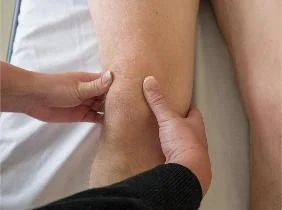

| Feel | Tenderness (General, Localized): Quadriceps, Patella, Patellar tendon, Tibial tuberosity, Origin, and insertion of collateral ligaments, ACL, MCL | Identify areas of pain and inflammation in relevant structures | Tenderness - General: Tenderness - Localized: Medial Structures (Tibial Tuberosity, Joint Line, Medial Tibial Condyle, Patella, Medial Femoral Condyle, Joint Space, MCL): ![]() Lateral Structures (Quadriceps, Patella, Tibial Tuberosity, Head of Fibula, LCL, Lateral joint line): ![]() | Localized pain upon palpation |

| Joint-line tenderness, medial and lateral | Assess for meniscal or collateral ligament pathology | Joint lines: ![]() | Pain upon palpation along the joint line | |

| Back of knee, baker’s cyst and tenderness | Further assess posterior knee for specific pathologies | Tenderness or swelling indicating a Baker’s cyst or other posterior pathology | ||